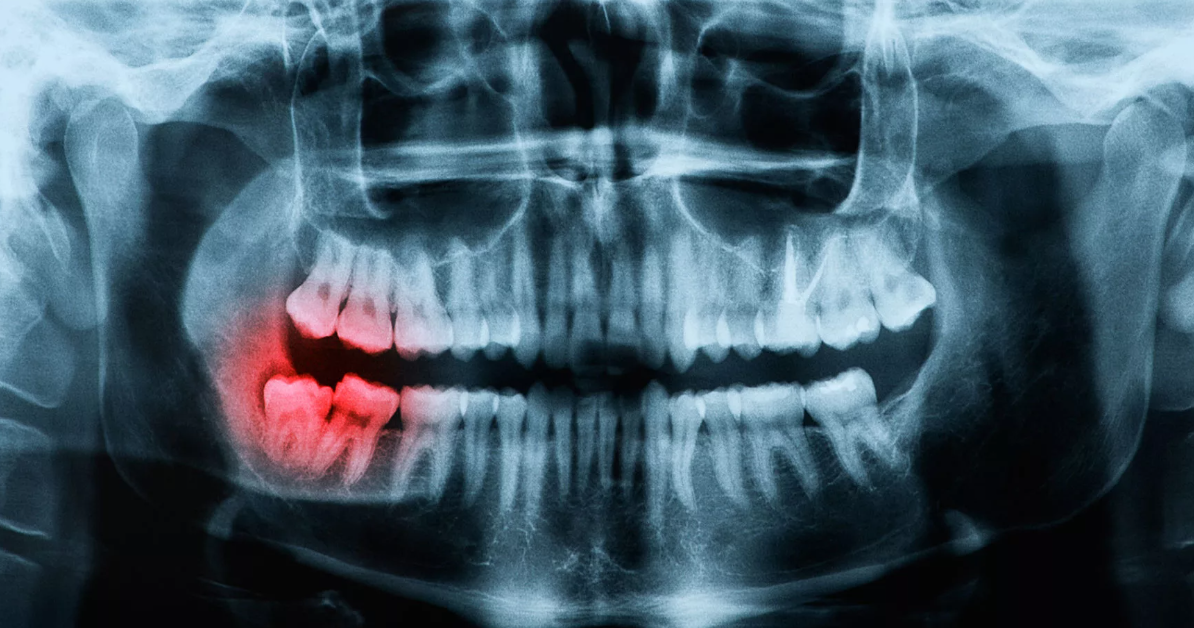

Кариес зуба мудрости: лечить или удалять

В современном медицинском понимании зубы мудрости (в стоматологии их называют восьмерки или третьи моляры – «жевательные» зубы) считаются рудиментом. То есть функционально не обязательной частью зубного ряда. Восьмерки практически не участвуют в пережевывании пищи, при этом нередко доставляют массу неудобств и болезненных ощущений – они режут десну и щеку, неправильно и не полностью прорезаются и так далее. И при этом являются отличным местом для размножения патогенных микроорганизмов, поскольку производить их тщательную гигиену весьма затруднительно. Поэтому в стоматологии достаточно распространено удаление зубов мудрости даже в тех случаях, когда у них нет кариозного либо иного инфекционного поражения. А в случае с кариесом – тем более.

Показания к удалению зуба мудрости с кариесом

• Если кариес не обнаружен на ранней стадии и уже намечена выраженная деградация и разрушение дентина, удаление зуба мудрости также является наиболее правильным решением.

• Дистопирование (неправильное положение) и ретинирование (неполное прорезание десны) восьмерки – еще одно показание к операции по ее удалению.